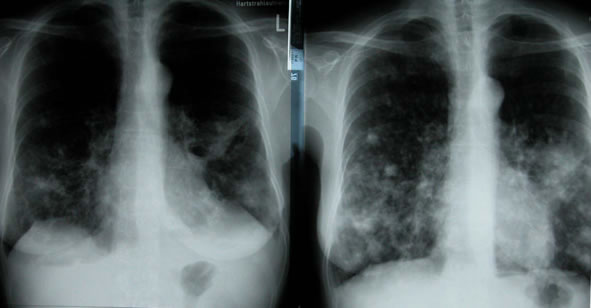

Lungenmetastasen

Einführung aktuelle Bilder - Einführung Demonstration